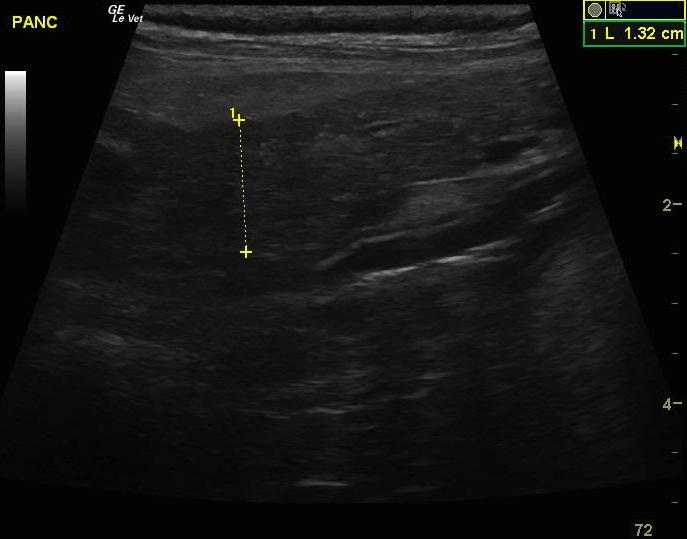

An 11 year-old MN Standard Poodle was presented for pyrexia, lethargy, and abdominal discomfort. Abnormalities on CBC and serum biochemistry were leukocytosis and severely elevated cPL. On radiographs, possible loss of detail of the cranial right quadrant was evident.